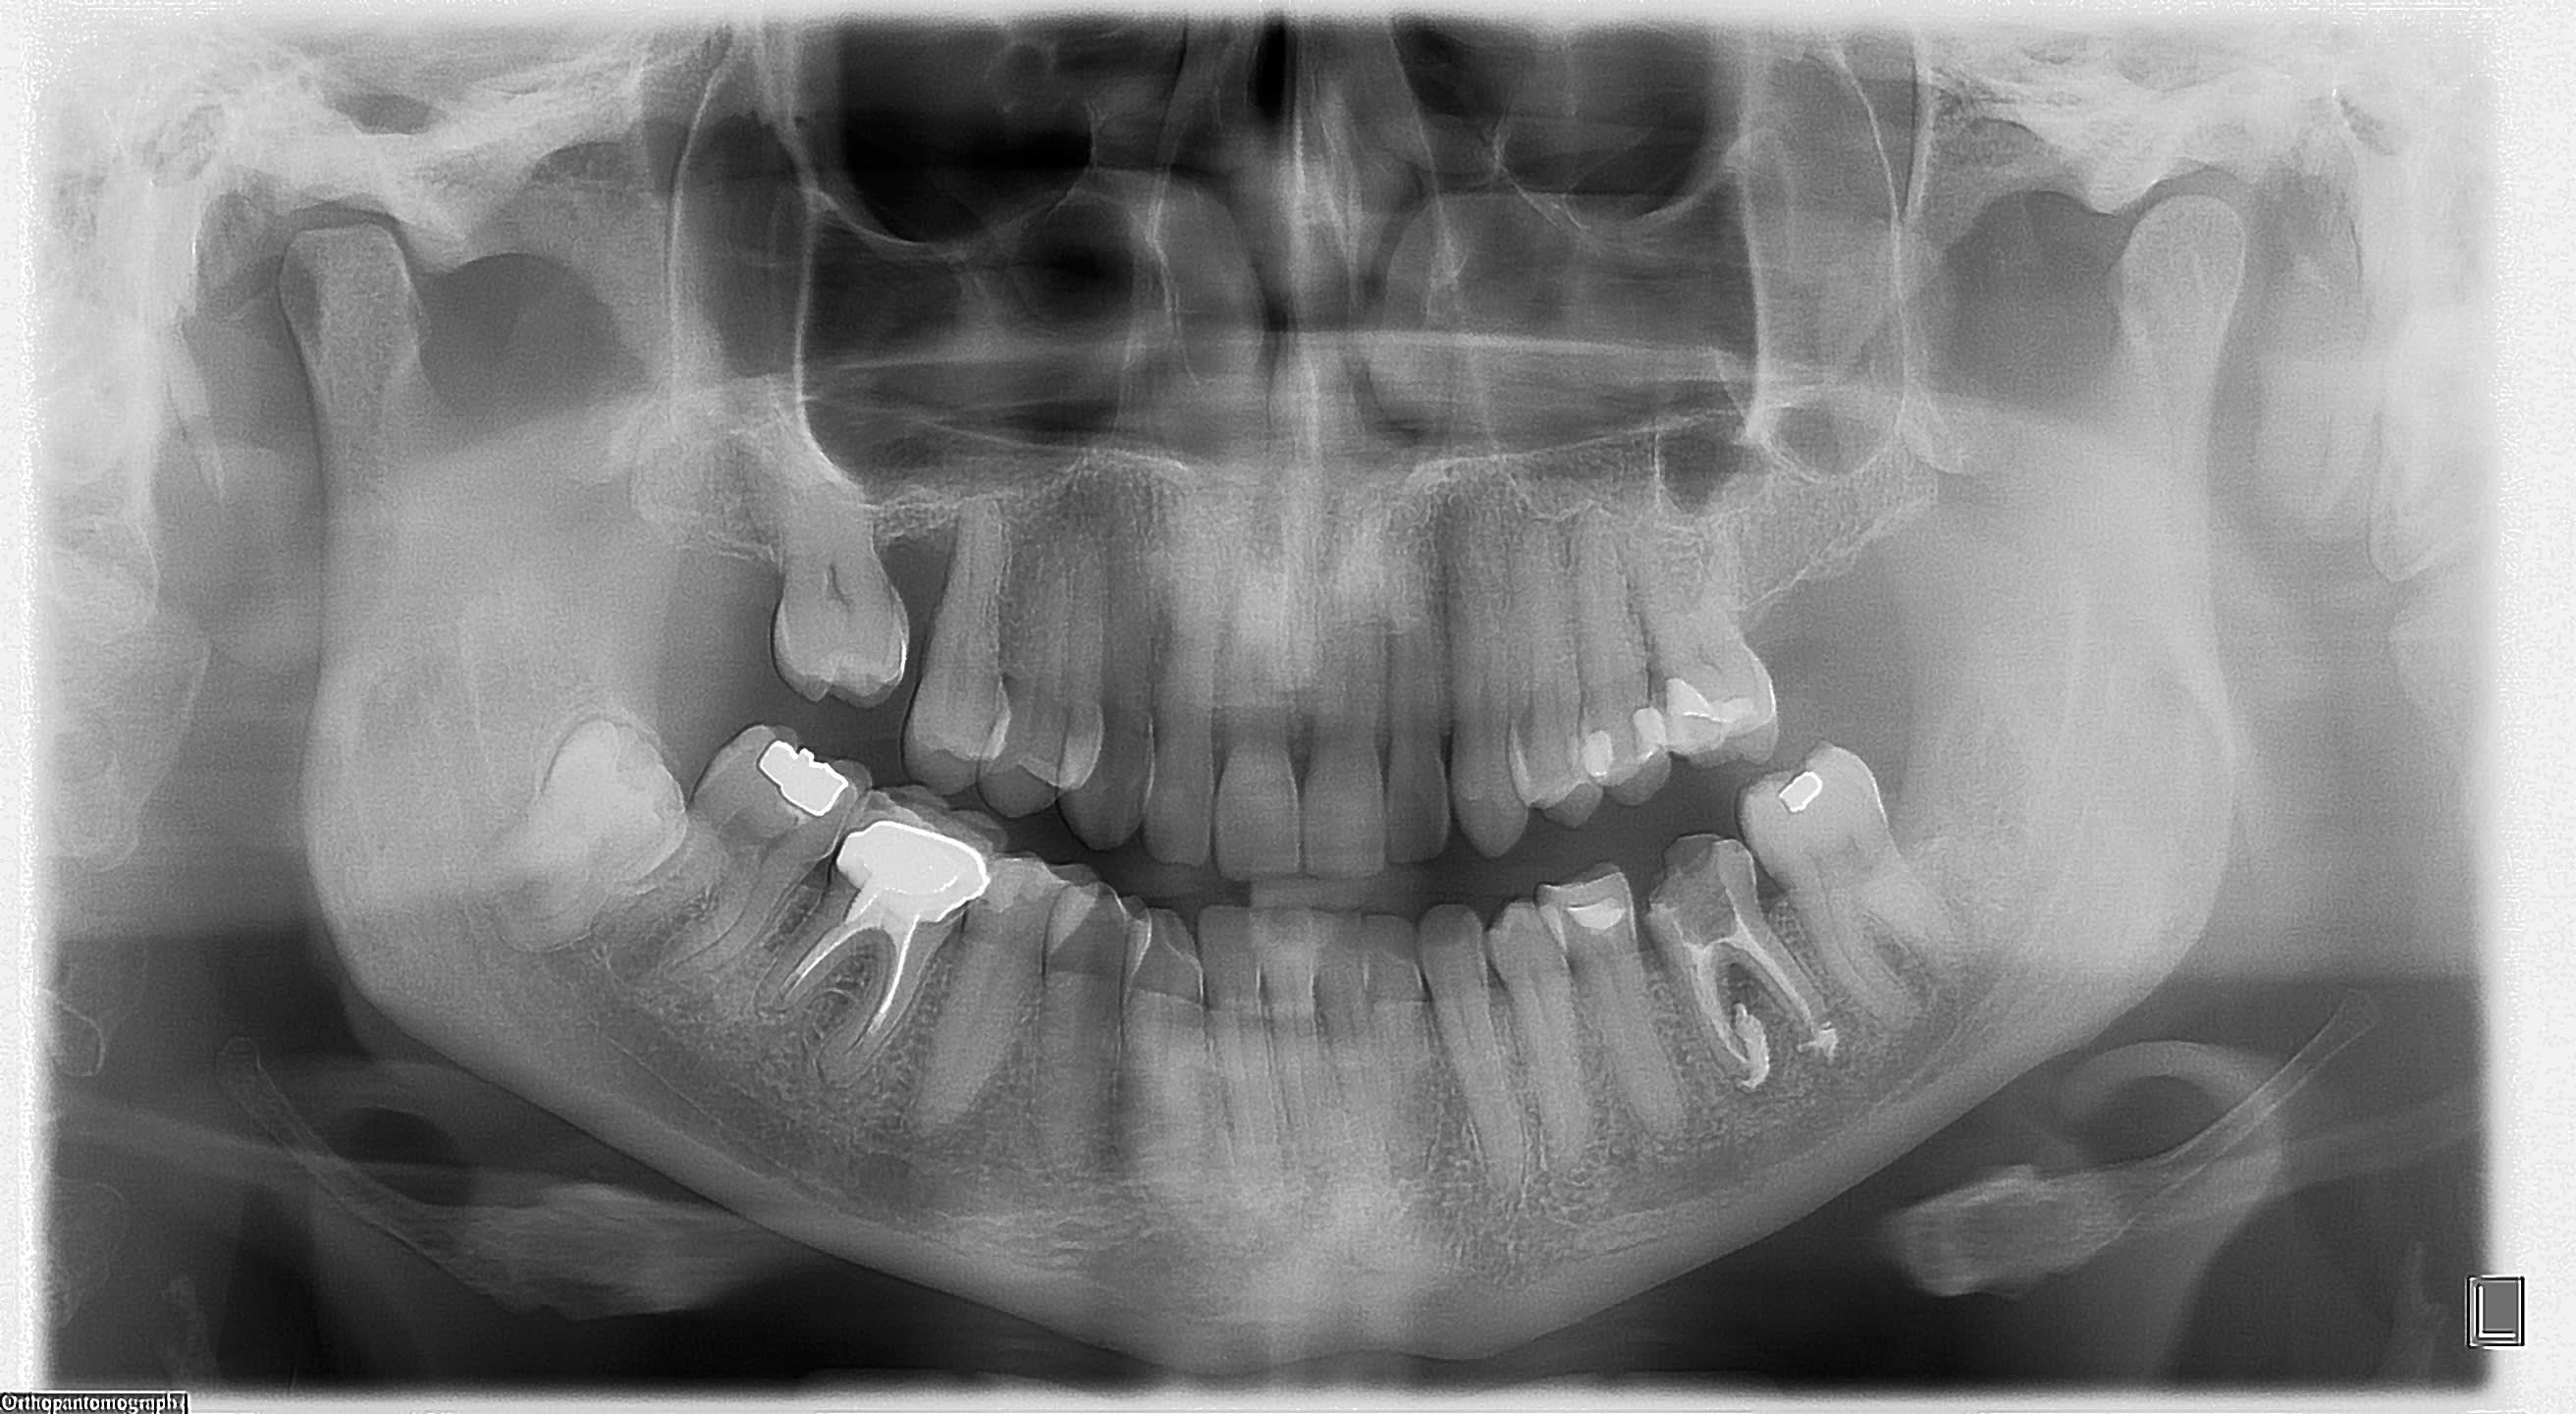

Je fais parvenir les radios panoramiques .

En revanche les apex semblent grands ouverts...

Dans tout ça ce qui me dérange le plus c est la distribution d antibio façon Haribo, sans respect des recommandations et la pano post opératoire...

quand tu fais un depassement sur une de ces dents, tu n'as jamais la trouille d'une atteinte du canal mdbulaire par le produit d'obturation?

Et une pano ici est totalement justifiée. L'irradiation d'une pano c'est deux retroalveloaitres et demi, alors le rayonnement , hein, dis, hein, c'est que dalle devant ceux et celles qui mitraillent en retro....